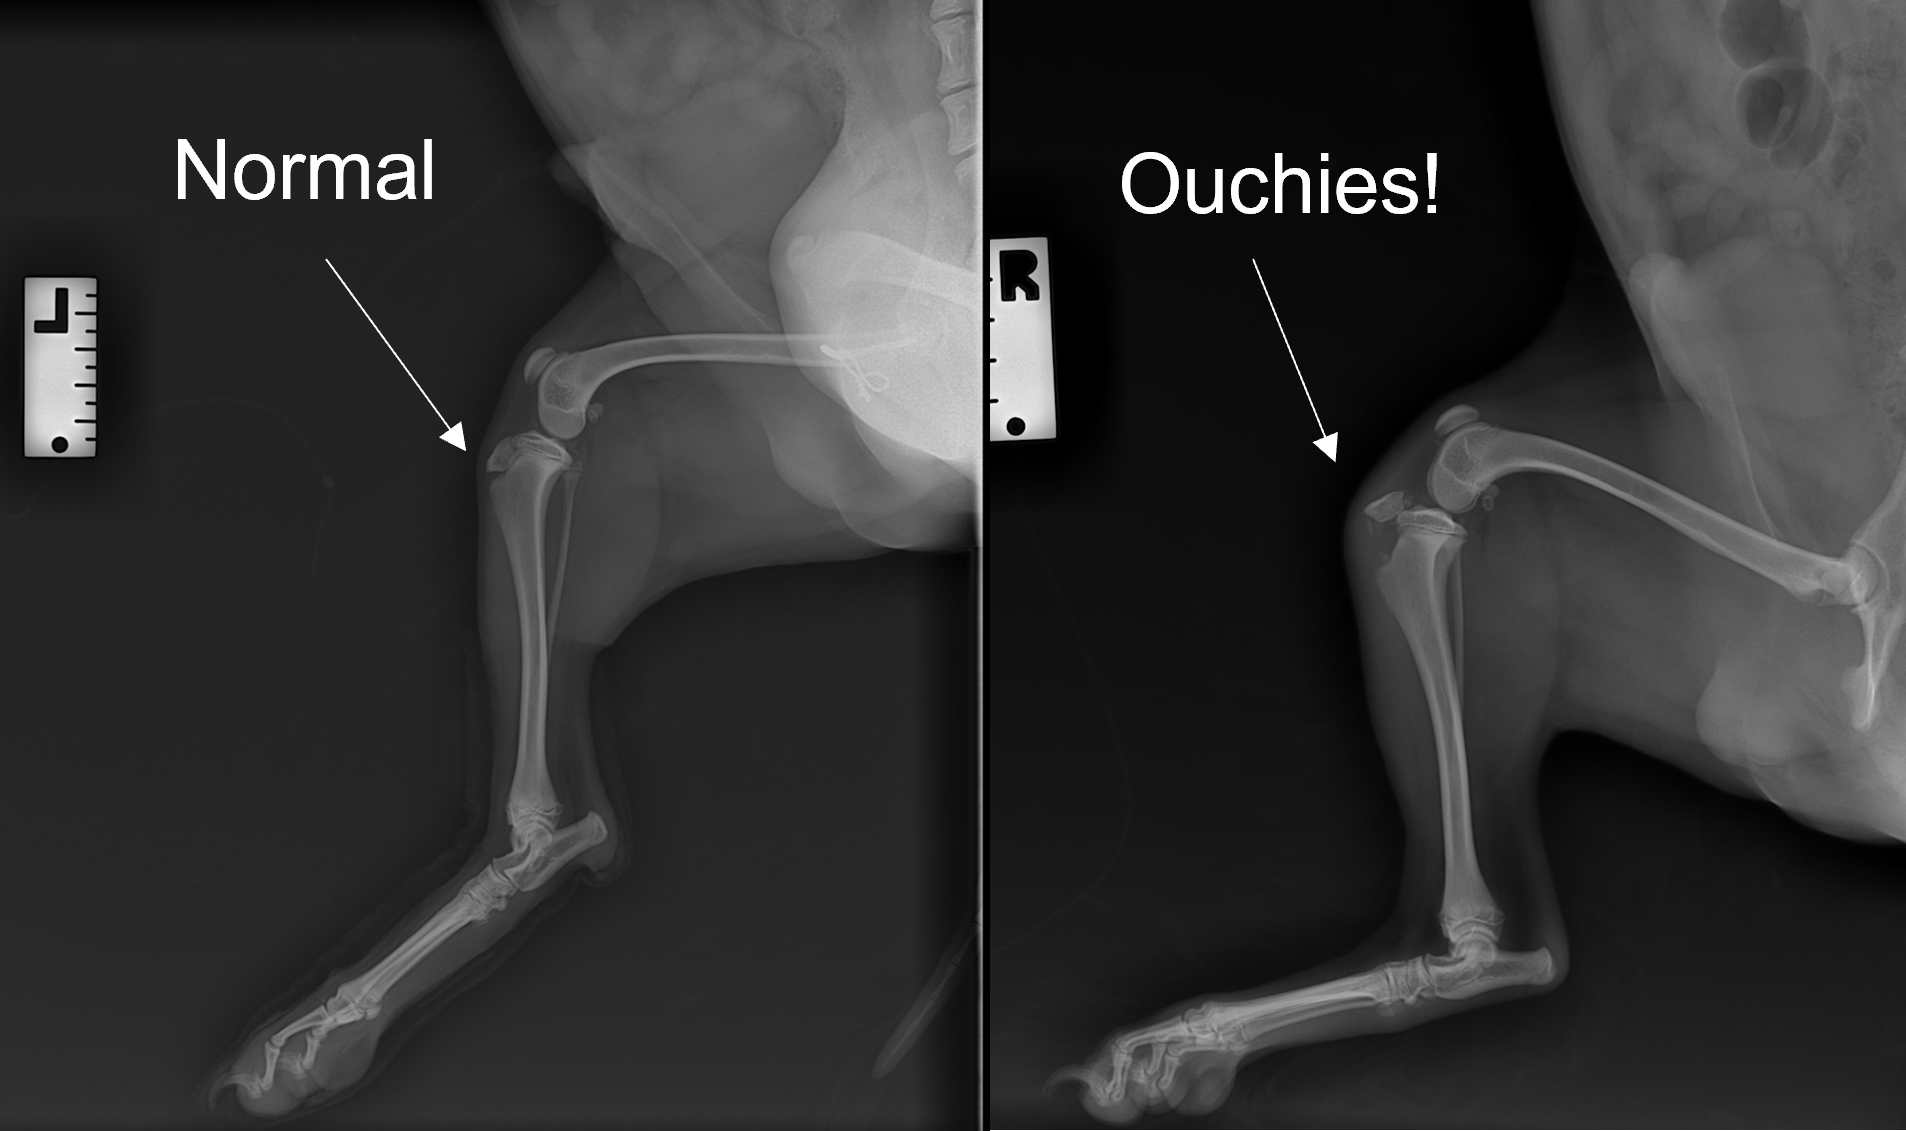

Outdoor cat lands in surgery after injury Dr Phil Zeltzman’s Blog Broken Knee Dog Cranial drawer is instability in the knee that occurs when the knee. Humans have a similar anatomical structure to the dog's knee, but the ligaments are called the anterior and. In an open fracture, you might even see the end of the bone poking out of the open wound in the skin. It's important to understand the difference in breaking. Broken Knee Dog.

Proximal tibial fracture in a 17week old puppy with open growth plates Broken Knee Dog A dog's broken leg may appear deformed or bent at an odd angle, especially if the pieces of a comminuted fracture have drifted out of their normal alignment. Veterinarians diagnose a fully torn crcl by noting cranial drawer. In an open fracture, you might even see the end of the bone poking out of the open wound in the skin.. Broken Knee Dog.

Tibial Tuberosity Avulsion Fracture in Puppies A Guide Broken Knee Dog It's important to understand the difference in breaking or spraining a leg for dogs. How veterinarians diagnose torn knee ligament in dogs. Veterinarians diagnose a fully torn crcl by noting cranial drawer. Humans have a similar anatomical structure to the dog's knee, but the ligaments are called the anterior and. Swelling and bruising may be apparent. Cranial drawer is instability. Broken Knee Dog.